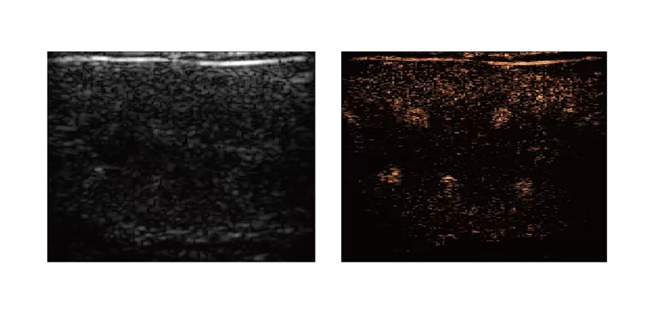

超分辨率超声成像

肿瘤微血管成像:异常微血管生长是癌症的特征之一,超分辨率超声成像可用于癌症的基础研究和临床管理,如早期检测、诊断和治疗反应评估。在肿瘤体积尚小时,通过微血管形态变化实现早期诊断

脑微血管成像:提供大脑范围的成像覆盖和微米级的空间分辨率,同时测量单个血管的血流速度,例如在脑卒中研究中早期检测缺血半暗带微血管血流变化,指导溶栓治疗。在阿尔茨海默病模型中观察淀粉样斑块区血管损伤,研究疾病机制